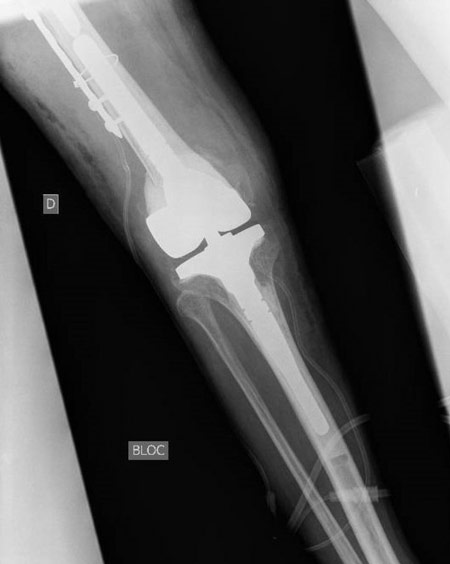

But... We noticed after removal of the drapes a massive knee instability that was not known before, and we asked for an x-ray.

A massive knee instability that was not known before

Internal fixation was impossible because there wasn’t enough bone distally. A Hinge TKR and a  bridging plate were fitted.

Internal fixation was impossible because there wasn’t enough bone distally